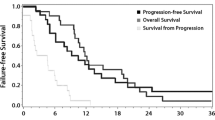

For differentiating tumor recurrence from therapy effect, adding DCE imaging to diffusion-weighted imaging (DWI) significantly improved AUC from 0.79 to 0.95 for reader 1 and from 0.80 to 0.96 for reader 2, respectively. There was no significant difference of AUC between the combination of DWI with DSC imaging and the combination of DWI with DCE imaging for both readers. With the combination of DWI and DCE imaging, the sensitivity and specificity were 86.7 and 88.1 % for reader 1 and 90.0 and 85.7 % for reader 2, respectively. The intraclass correlation coefficient (ICC) between readers was highest for calculation of the 90th percentile histogram cutoffs for IAUC (ICC, 0.87).

Adding perfusion MR imaging to DWI significantly improves the prediction of recurrent metastatic tumor; however, the diagnostic performance is not affected by selection of either DSC or DCE MR perfusion method.